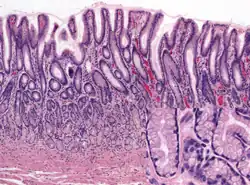

Histology of normal fundic mucosa. Fundic glands are simple, branched tubular glands that extend from the bottom of the gastric pits to the muscularis mucosae; the more distinctive cells are parietal cells. H&E stain.

Histology of normal antral mucosa. Antral mucosa is formed by branched coiled tubular glands lined by secretory cells similar in appearance to the surface mucous cells. H&E stain.